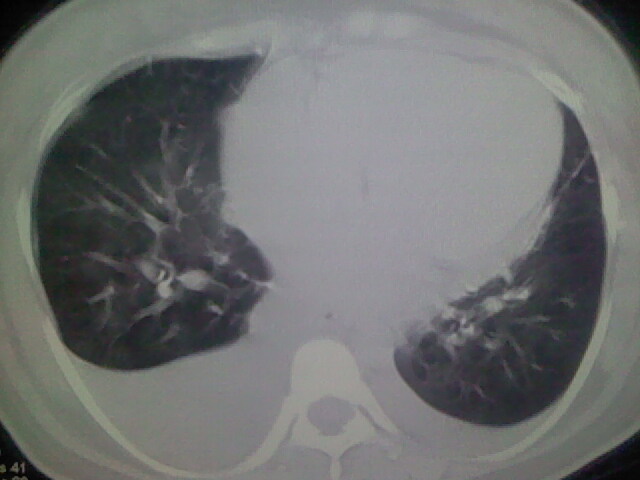

女,24,剖腹产后,突觉胸痛,干咳,不能平卧

肝脾大,双侧胸腔积液,双肺水肿,肺动脉[包括远端小动脉],左右心房,左心室增宽,右心室主动脉无明显改变,符合左心功能不全征;;建议除外二尖瓣关闭不全,扩张性心肌病

全心衰导致积液、肺水肿。不知手术前有无心脏病变?

产后心衰

肺水肿,双侧胸腔积液,心影增大.考虑妊娠心脏病